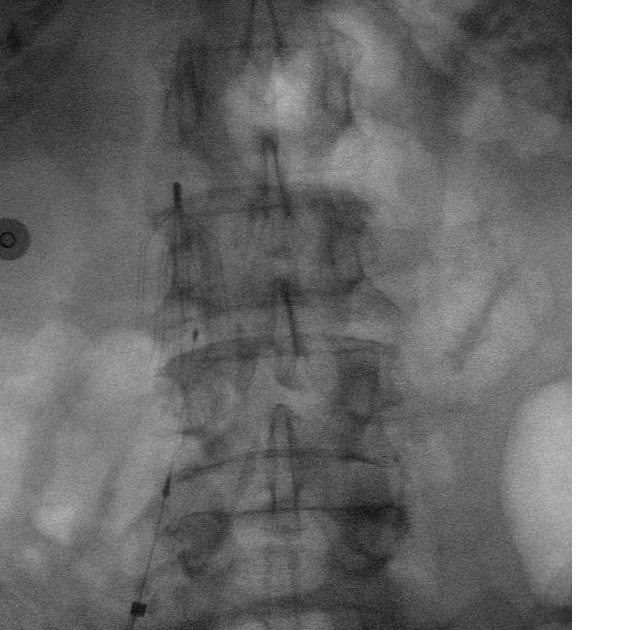

Abdomen xray filter in the IVC which prevents clots from traveling Ivc Filter On X Ray Inferior vena cava filters are devices used to prevent blood clots from traveling to the lungs. Inferior vena cava (ivc) filters are placed in patients who have a history of or are at risk of developing blood clots in the legs, including. Inferior vena cava (ivc) filters are a controversial mechanical adjunct in the prevention of pulmonary embolism, the most. Ivc Filter On X Ray.